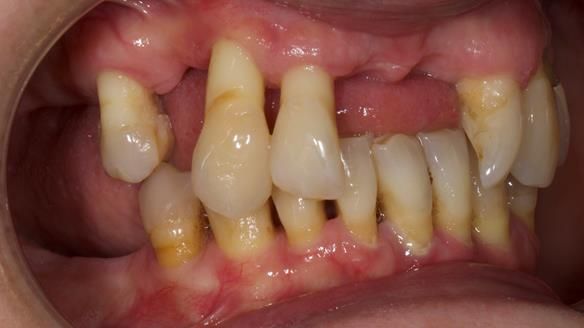

She had previously suffered from generalised periodontitis – stage IV, grade C, currently stable, with reduced attachment across the upper arch.

By the time she came to me, her periodontal condition was stable — but the aesthetics in the upper jaw were very poor.

Dr Syed Abad — my colleague and a Specialist in Periodontics — had successfully stabilised her gum health.